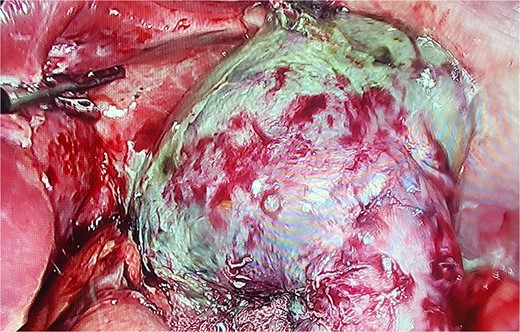

On laparoscopy, about 200 ml of purulent fluid was discovered around the liver, so a leak was suspected. Nonetheless, as we retracted the liver, we found a complete gastric remnant necrosis; the anastomosis was intact, with no evidence of fistula, but the remnant stomach was discolored, necrotic, and thinned from the fundus to the antrum (Figs 1 and 2). The spleen appeared normal and was not compromised in any way. Pathology confirmed the diagnosis, as extended necrosis and infarction was seen in the gastric wall. Gastric remnant necrosis was the final diagnosis.

Laparoscopy, gastric remnant is seen with necrosis and purulent fluid.

The gastric remnant is seen with necrosis and dissected from the spleen.